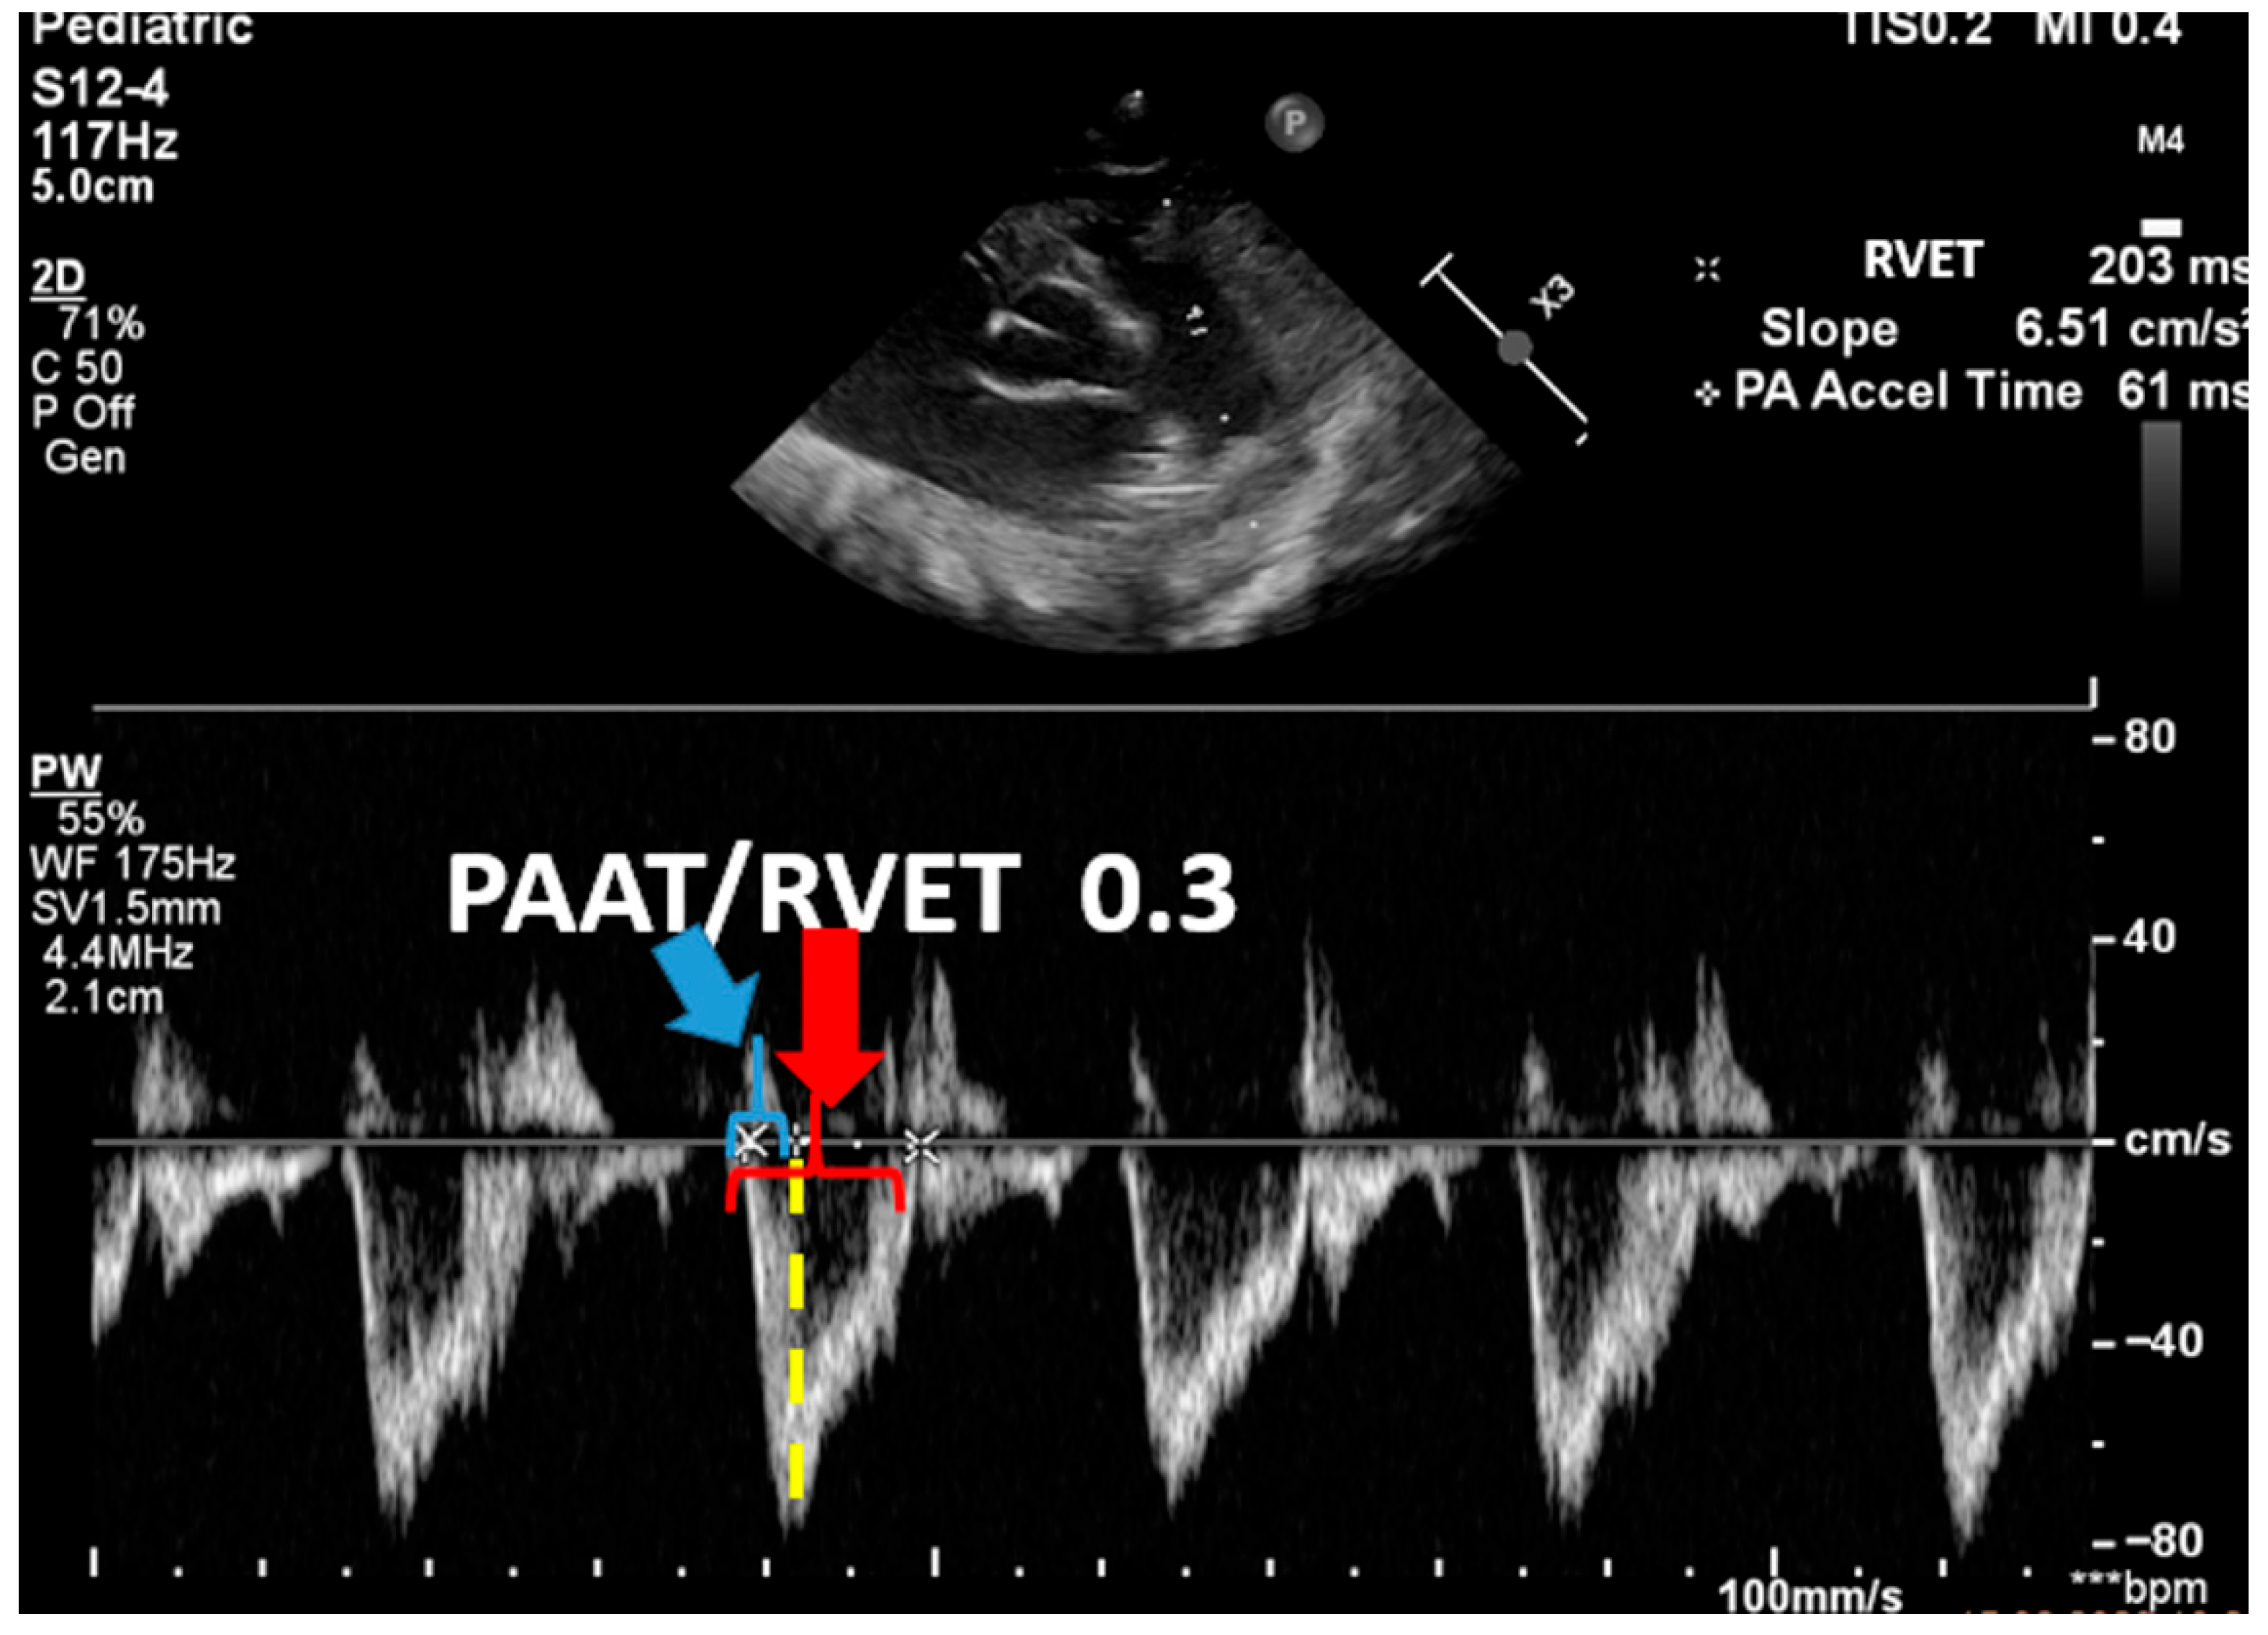

| Advanced ECHO and Hemodynamic Evaluation | RV fractional area change (FAC %) Pulmonary arterial acceleration time (PAAT) and PAAT/RV ejection time ratio Speckle tracking and strain rate Estimation of left and right cardiac output and serial assessment to see the response to therapy | Helps evaluate cardiac function and response to therapy |